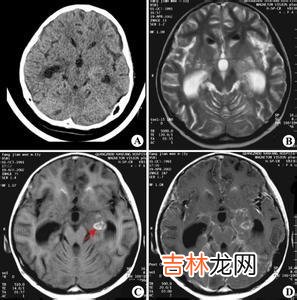

文章插图